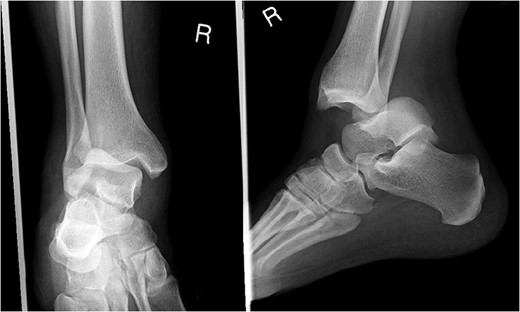

A 30-year-old male patient presented to Emergency Department (ED) following a run over injury. The patient described the mechanism of injury as moving his body over his run over foot. On clinical examination, there was obvious deformity and swelling of the right ankle. Dorsalis pedis pulse was felt but weak compared to the contralateral side with a capillary refill time under 3 s. The posterior tibial artery could not be palpated because of the deformity. X-rays showed posterior ankle dislocation without associated fractures (Fig. 1). Urgent reduction of the dislocation was done under sedation in ED. The knee was first flexed to relax the tendon Achilles then longitudinal traction with gentle forward force applied to the heel with immediate reduction of the deformity achieved. The foot was reassessed for vascular status. Triphasic pulse in both drosalis pedis and posterior tibial artery was detected with hand held Doppler. Ankle was immobilized in posterior below knee back slab to accommodate for swelling and check x-rays confirmed reduction of the ankle joint (Fig. 2). CT scan was done afterwards to define any subtle incongruity or osteochondral fragments entrapped in the joint. CT did not show any associated fractures and showed congruent reduction of the ankle joint (Fig. 3). Patient was mobilized touch weight bearing for first 2 weeks. The back slab was changed for weight bearing short leg cast and progressive weight bearing was allowed for the following 4 weeks. At 6 weeks follow up, plaster was removed and on examination patient still had moderate tenderness over the medial joint line and deltoid ligament area. Also, patient had limited range of plantar and dorsal flexion. Referral for physiotherapy was done for start of functional rehabilitation and range of motion exercises and in mean time MRI was done to delineate extent of ligamentous injury. MRI showed bone bruising of the lateral malleolus, medial malleolus and lateral talus (Fig. 4). The anterior talufibular ligament (ATFL), calcaneofibular ligament (CFL), posterior talofibular ligament (PTFL) and deltoid ligaments were sprained but intact. At 12 weeks follow up, patient could walk normally without any symptoms of instability and achieved 20° of both plantar and dorsal flexion. At 16 weeks, patient achieved full range of motion of ankle and was able to return to work. At 24 weeks follow up patient was able to resume his sport activates as preinjury level.

Post reduction CT scan showing congruent reduction of the dislocation without associated fractures.